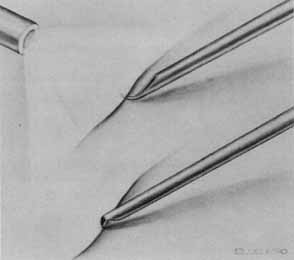

Functional testing has been used to help differentiate pseudoholes or other lesions from true macular holes. The Watzke-Allen sign was one of the first such functional tests.14 This test is performed by presenting a narrow slit beam over the suspected macular hole. The patient is then asked to describe what he or she perceives. If the patient describes a break in the line, a full thickness hole should be suspected (Fig. 1). Another method of performing this test is to pass the slit beam slowly over the macula from varying angles. If the patient perceives a break in the line, at any time, the test is considered to be positive (i.e., there is a full-thickness macular hole).